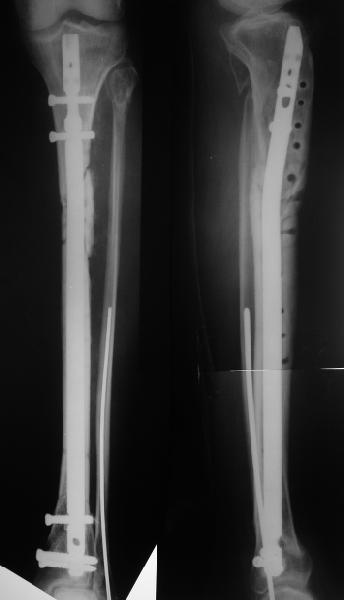

Декабрь 200322 июня 2004

В декабре прошлого года обсуждался случай бамперного перелома голени, когда молодой женщине в одной из больниц Москвы неудачно был выполнен остеосинтез гвоздем - это обсуждение можно просмотреть здесь, снимок тогдашний прилагаю.

Вчера поступила к нам в отделение. Клинически определяется приличная подвижность, градусов 35 в переднезаднем направлении. На снимках еще видны фиксированная тоникм стержнем уже сросшаяся малоберцовая кость, и тоже сросшийя перелом дистального метадиафиза большеберцовой костибез признаков хирургической фиксации (?). Сегодняшний снимок также в приложении.

Планируем удаление пластинки и закрытый интрамедуллярный остеосинтез с рассверливанием.

Еще раз спасибо! Сделали вчера. Все прошло по плану, интраоперационное фото после удаления пластинки и итоговые снимки прилагаю. Гвоздь бесканальный 12 мм. Сегодня пациентка уже ходит по палате с одним костылем.